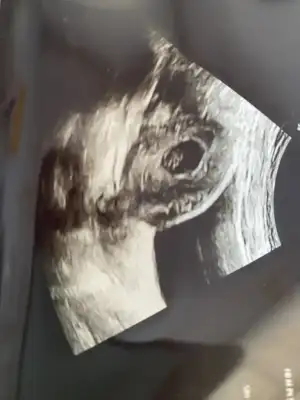

Vajınal kuzum . Ama 10 gun once sağdaydı sımdı solda gezıyor heraldeBu vajinal mı canım vajinal ise kıza benziyor

Soldaki kız canım sagdaki tam emin olmamakla erkek olabilirSeni birde ben darlayabilir miyim ikizlervajinal bakıldı Eki Görüntüle 3252790

10 gün öncesini tekrar at bakim kuzum karından mı oVajınal kuzum . Ama 10 gun once sağdaydı sımdı solda gezıyor heralde![]()

Yok kuzum buda vajına10 gün öncesini tekrar at bakim kuzum karından mı o

Kız senin bebek bildigin yer degiştirmiş yaYok kuzum buda vajına